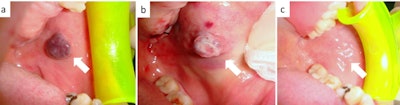

A 64-year-old man

A 64-year-old man with occasional biting trauma had a blue-violet, immobile, painless, and nonbleeding lesion of the cheek for a year. He was prescribed the blood thinner warfarin for chronic atrial fibrillation. An ultrasound scan confirmed his diagnosis of venous malformation. The man underwent transmucosal photocoagulation by diode laser without suspending his warfarin treatment. He received a small amount of local anesthesia, and a laser was used to photocoagulate the lesion directly. Treatment ended when the lesion's color changed to grayish-white. It healed in 14 days without recurrence.